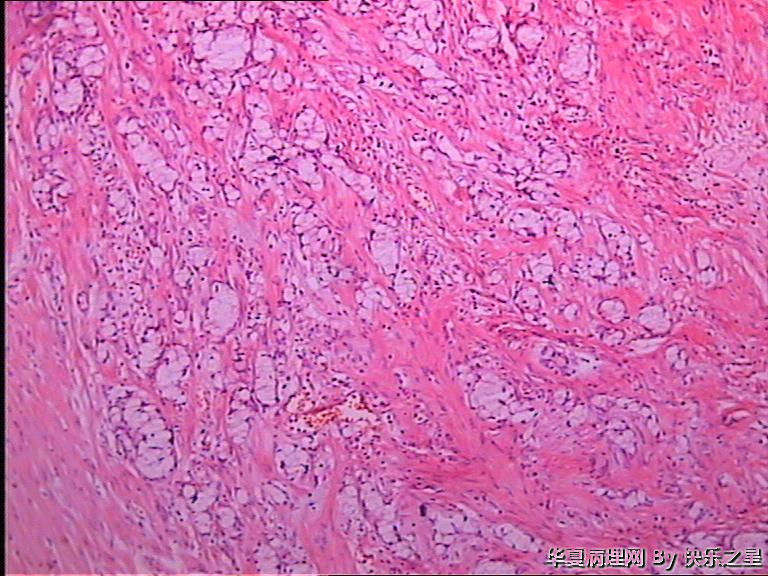

阑尾杯状细胞腺类癌?

• 阑尾杯状细胞腺类癌?图2

图2

首选转移性阑尾杯状细胞类癌鉴别印戒细胞癌

杯状细胞类癌 IHC Syn   cgA  NSE  CK  LI67

应该是类癌,正常腺体不会在肌层内浸润。